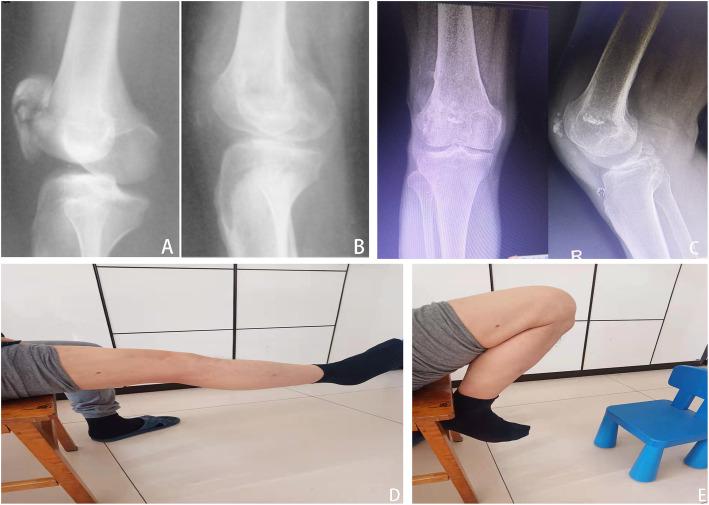

Between January 1987 and December 2003, this retrospective study included a total of 35 patients (mean age, 51.4±16.8 years) with a minimum of 10 years follow-up period, comprising 29 males and 6 females, who were divided into the total patellectomy group (17 patients) or the open reduction and internal fixation (ORIF) group (18 patients) in the Third Affiliated Hospital of Hebei Medical University. We retrospectively collected patient demographics and data on the type of trauma, fracture type, and postoperative complications. Clinical outcomes including knee range of motion (ROM), 36-Item Short-Form Health Survey (SF-36) score [including physical component score (PCS) and mental component score (MCS)], Knee Injury and Osteoarthritis Outcome Score (KOOS), and Kujala score were evaluated and compared between the two groups. Biodex System dynamometer was used to quantitatively evaluate quadriceps femoris muscle power following measurement of peak torque.

RESULTS

The mean follow-up periods of the total patellectomy group and the ORIF group were 17.2±5.6 and 16.8±4.9 years, respectively. There were no significant differences between the two groups of patient demographics in terms of the number of patients, age, sex, injury side, time to surgery, type of trauma, and fracture classification (p>0.05). Total patellectomy was comparable to osteosynthesis with tension band wiring in terms of ROM [injured knee: 120.4±3.1° vs 118.6±3.3°; uninjured knee: 126.5±2.8° vs 127.3±1.7°; both p>0.05], peak torque [Injured knee: 96.2±2.3 vs 97.3±2.6, N· m; Uninjured knee: 107.6±2.1 vs 106.3±1.8, N· m; both p>0.05], SF-36 score [PCS: 64.1±18.0 vs 61.5±17.9; MCS: 55.1±13.8 vs 54.3±12.4; both p>0.05], KOOS score [76.3±12.1 vs 73.4±11.7; p>0.05], and Kujala score [67.6±11.8 vs 70.8±11.9; p>0.05] at the final follow-up, while total patellectomy had significantly shorter operation time than ORIF group (47.5±12.1 vs 68.8±22.3, min, p<0.05). In the total patellectomy group, complications occurred in 6 of 17 cases (35.3%), and all occurred with calcification. In the ORIF group, complications occurred in 12 of 18 cases (66.7%), including 2 cases of infection (11.1%), 1 case of non-union (5.6%), 2 cases of implant failure (11.1%), 2 cases of soft tissue irritation (11.1%), and 5 cases of patellofemoral arthritis (27.8%).

CONCLUSIONS

Total patellectomy technique was a safe and reliable alternative treatment for treating patients with highly comminuted patella fractures when anatomically reduction and rigid fixation were difficult, although it caused relatively higher rates of calcification.